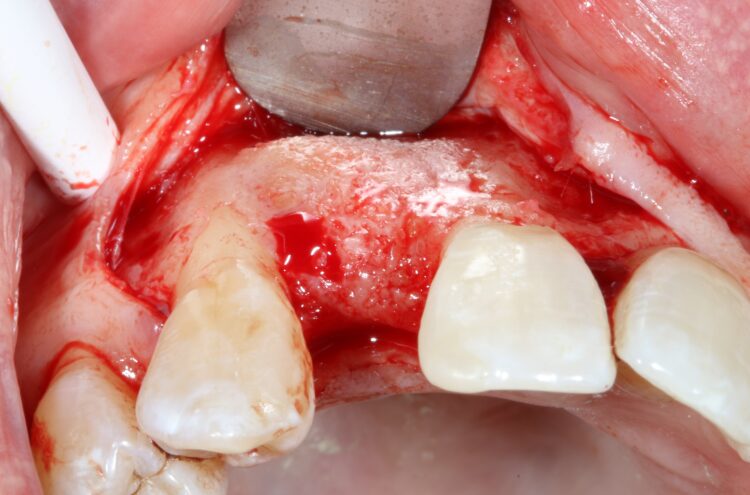

The first treatment phase included the elevation of a large full thickness flap to fully expose the area and enable the harvesting of autogenous bone utilising a safescraper.

The UR2 was then removed including excavation of all granulation tissue, taking care to avoid any direct curettage of the exposed UR3 root. The large bone defect was then filled with a 50/50 mix of autogenous bone chips and an allograft (MinerOss®, a cortico-cancellous mix – BioHorizons Camlog) and the buccal defect was covered with a native porcine collagen membrane with a high percentage of collagen type III for a prolonged barrier function of six months. No fixation pins were used.

The concept was that this exposed membrane would provide a barrier and prevent loss of the bone graft, but would also break down rapidly, favouring early epithelialisation of the open wound by secondary intention healing.

The occlusal aspect of the bone graft – which would remain exposed during the healing period – was covered with a shorter acting native collagen membrane. The concept was that this exposed membrane would provide a barrier and prevent loss of the bone graft, but would also break down rapidly, favouring early epithelialisation of the open wound by secondary intention healing.

The muco-periosteal flap was sutured back with 6.0 Prolene and no attempt was made to coronally advance the flap for complete closure. The rationale was to maintain the open socket wound and thereby preserve the original mucogingival relationship with no alteration. The socket entrance was sealed with the short acting membrane, while the original tooth (after root removal) was utilised as a temporary pontic and bonded to the adjacent teeth with flowable composite.